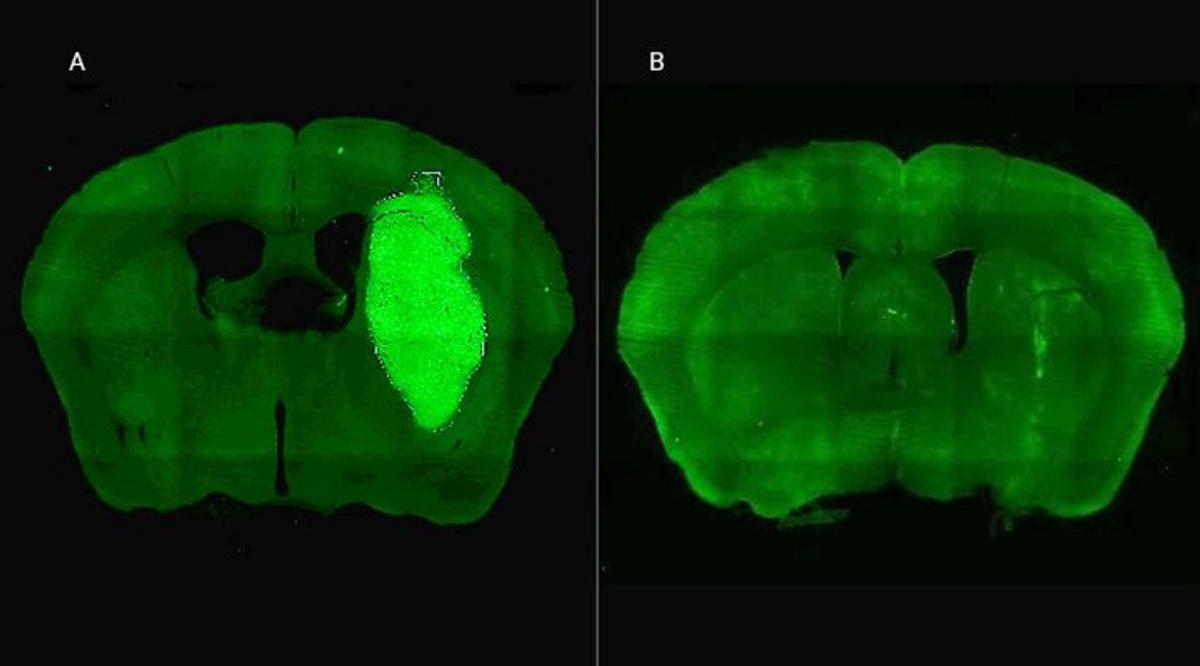

Especialistas del Consejo Nacional de Investigaciones Científicas y Técnicas (CONICET) identificaron una nueva estrategia terapéutica para frenar el desarrollo del glioblastoma, la cual en estudios in vitro y preclínicos logró volverlo más sensible a la quimioterapia y la radioterapia. El avance se describe en la revista Life sciences.

Desde el CONICET explican que el glioblastoma es el tumor cerebral primario maligno más común en adultos. Esta enfermedad conlleva un pronóstico desalentador debido a su naturaleza altamente invasiva y resistencia a la quimioterapia y radioterapia. La mediana de supervivencia estimada de los pacientes con este tipo de tumor es de 9 meses, y la tasa de supervivencia a 5 años es de tan solo el 7 %.

“Descubrimos que el bloqueo de una proteína llamada Foxp3, que se expresa en las células del glioblastoma, potencia la efectividad de la quimioterapia y la radioterapia. Los resultados del estudio son alentadores para quienes desde la ciencia buscamos aportar al desarrollo de opciones terapéuticas reales y efectivas para los pacientes con este tumor. La estrategia terapéutica se probó con éxito en estudios in vitro y preclínicos y sin duda nuestra esperanza es que se pueda probar en ensayos clínicos en el futuro, pero aún son necesarias investigaciones adicionales para llegar a eso”, afirma Marianela Candolfi, líder del trabajo e investigadora del CONICET en el Instituto de Investigaciones Biomédicas (INBIOMED, CONICET-UBA).

Candolfi y colegas utilizaron una terapia génica experimental basada en una molécula muy pequeña o péptido llamado P60, desarrollado por Juan José Lasarte en la Universidad de Navarra, en España, que atraviesa la membrana celular e inhibe la proteína Foxp3. “Cuando en experimentos de laboratorio bloqueamos Foxp3 utilizando P60, la respuesta de las células de glioblastoma a la radioterapia y a una variedad de drogas quimioterapéuticas mejoró notablemente”, destacó la investigadora del CONICET.

Además, P60 tuvo efectos antitumorales directos, reduciendo la viabilidad y la migración de las células de glioblastoma e inhibiendo la proliferación de células endoteliales que son clave para la progresión del tumor. Para evaluar estos efectos, los autores del estudio utilizaron una variedad de modelos celulares murinos (de roedor) y humanos. “En particular, los cultivos derivados de biopsias de pacientes con glioblastoma desarrollados por nuestro colaborador Guillermo Videla Richardson, del Instituto FLENI, son muy útiles para representar la heterogeneidad de estos tumores”, indicó Candolfi.